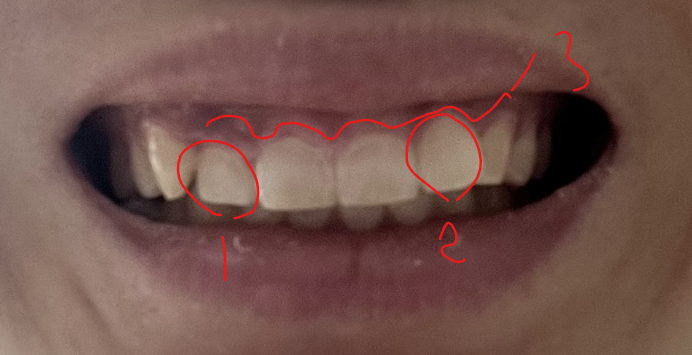

사진중에 1,2 표시한 부분이 덧니가 약간 있습니다.

또한 3 표시한 부분과 같이 잇몸이 약간 내려와 있어서 웃을때 잇몸이 많이 보인다고 생각할수 있을것 같습니다.

치료는 부분교정으로 1,2를 바르게 한 다음 교정치료 마무리 되어 갈때 3 부위 잇몸성형이 마무리 되어야 될것 같습니다.

혹은 1,2를 먼저 바르게하고 3은 교정치료후 결과를 보고 결정을 해도 됩니다.